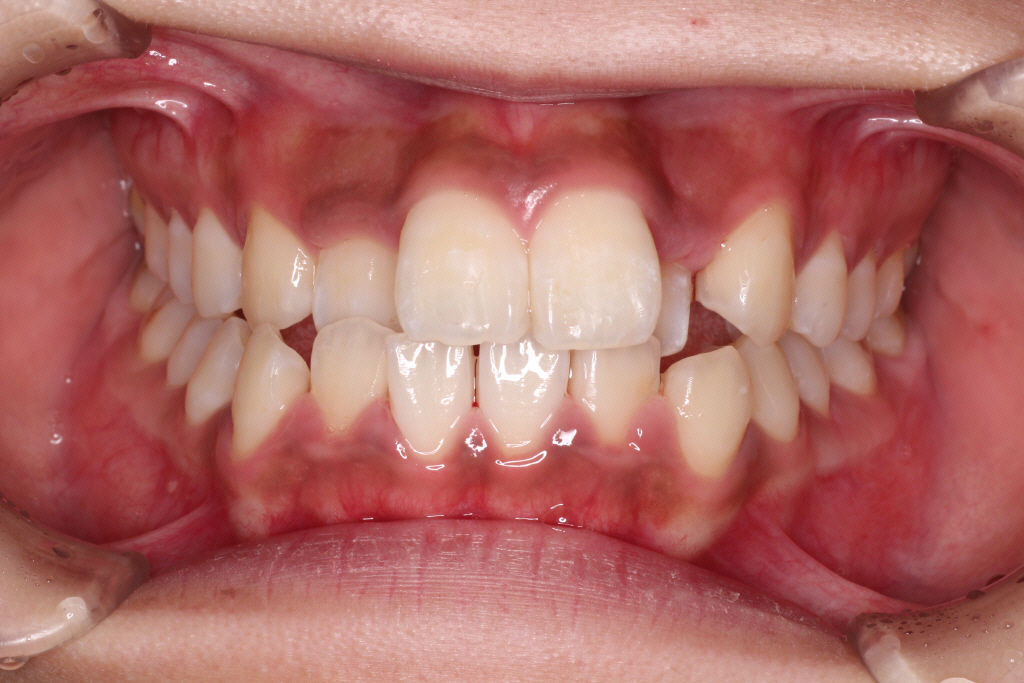

初診時のお口の中の状態です。

上の前から2番目の歯が下の歯列より内側にあり叢生です。

側方の上下の咬合関係が理想の上1本に対して下2本の理想的な噛み合わせではない。

歯列の幅がせまい。